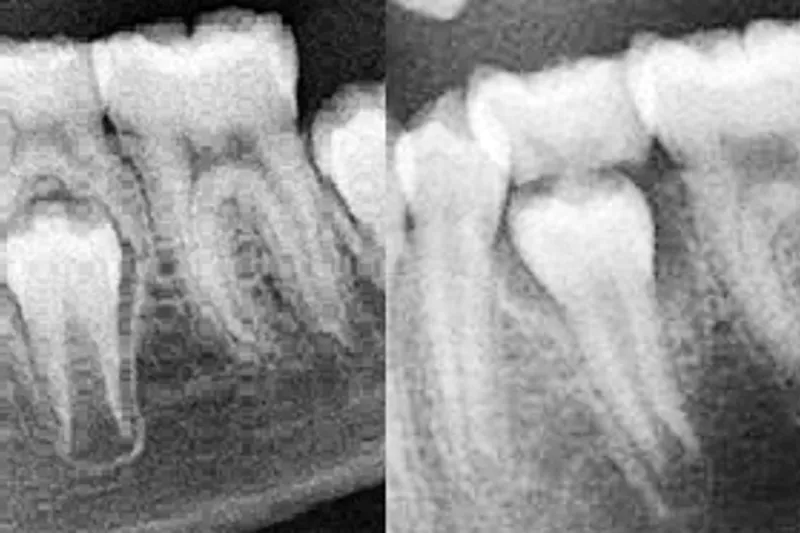

I denne oversigtsartikel belyses den fysiologiske resorption i det primære tandsæt i forbindelse med det normale tandskifte hos børn og unge. Desuden fokuseres der på de fænotypiske afvigelser, der ses ved patologisk resorption. Patologiske afvigelser kan dreje sig om uventet aggressiv resorption, om aggressiv resorption med kendt ætiologi eller om manglende resorption. Fire forskellige typer af uventet aggressiv resorption beskrives, og der gives et enkelt eksempel på aggressiv resorption som følge af traume (kendt ætiologi). Manglende resorption ses i tilfælde, hvor de primære tænder ikke resorberes. Dette beskrives ved tre eksempler. Årsager til normal fysiologisk resorption og til de patologiske afvigelser fra det normale resorptionsmønster er stort set ukendt. Nyere studier viser, at der er en medfødt biologisk disposition for patologisk rodresorption. Et forhold, der i fremtiden bør belyses genetisk.

In this overview, physiological resorption of the primary dentition in connection with the normal development of the permanent dentition is described. In focus is also the phenotypic pattern of pathological resorption. Pathological resorption can be either unexpected aggressive resorption, a aggressive resorption with a known aetiology, or lack of resorption. Four different forms of unexpected aggressive resorption are described, and a single example of aggressive resorption following trauma (known aetiology) is given. Lack of resorption is seen in cases, where the primary teeth do not resorb. This is described in three examples. The aetiology behind normal physiological resorption and the pathological deviations from the normal pattern of resorption are seemingly unknown. The aetiology behind resorptions needs to be elucidated in the future.